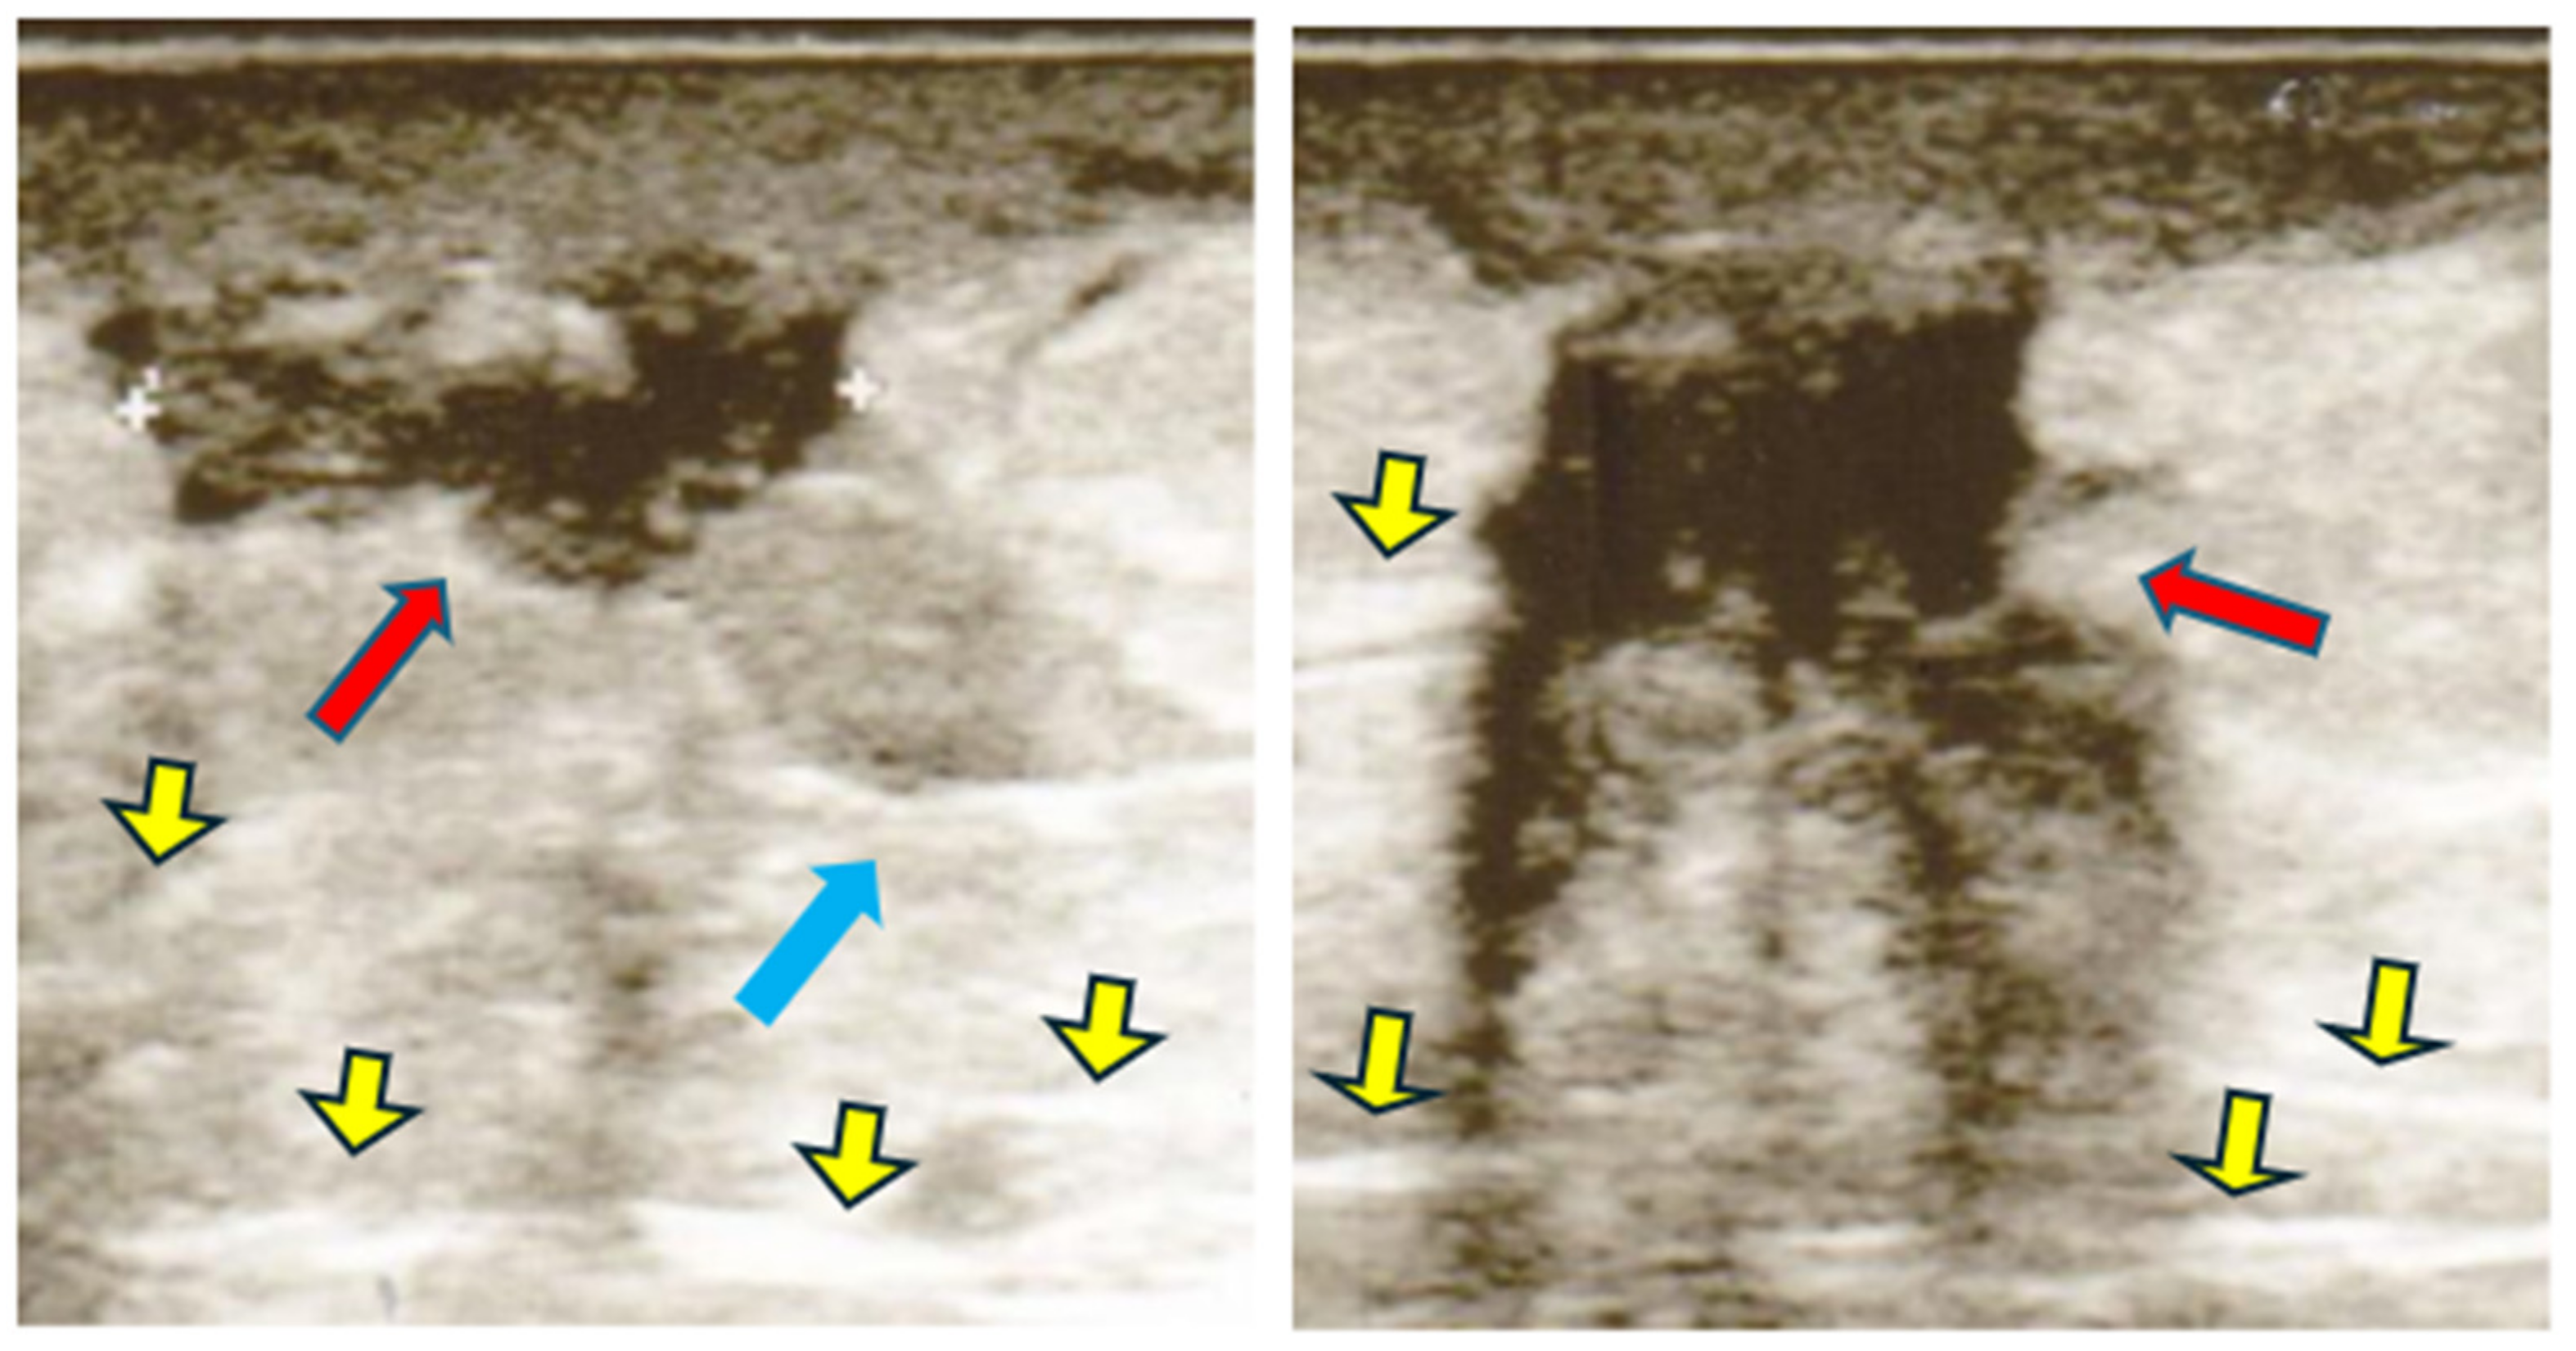

2.2. Ultrasonography

- -

- Hyper type A: iso-hyperechogenic with predominantly fibrotic component.

- Isotype B: isoechoic associated with small edematous islands delimited by fibrous stripes.

- Iso-hypo type C: iso-hypoechoic without fibers.

Ultrasonographic characteristics of LH

| 15.3% 29.2% 65.0% | 14.8% 20.2% 55.5% | 47.3% 22.4% 30.3% |